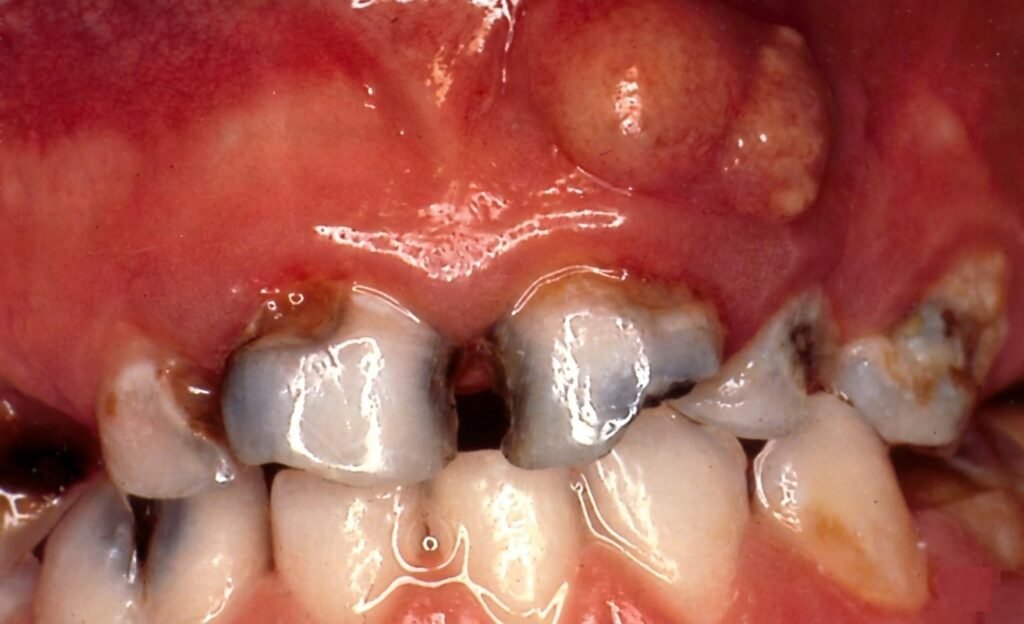

- Pulpite chronique granulomateuse :

- Destruction importante de la couronne avec des proliférations hyperplasiques du tissu conjonctif pulpaire de diverses dimensions ou un polype pulpaire unique pouvant combler la chambre pulpaire ;

- Symptomatologie pauvre et douleur à la mastication.